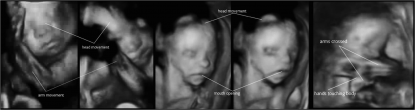

volti fetoUna recente ricerca approvata dall’Ethical Committee of the University of Dundee ha dimostrato che i feti nel grembo materno muovono la testa, le braccia e la bocca con più frequenza quando la mamma tocca l’addome, mentre questi movimenti decrescono usando solo la voce.

graficoLe donne sono state monitorate con un sistema a ultrasuoni capace di catturare anche l’espressione facciale dei bimbi.

In questo modo sono stati codificati i movimenti di:

• braccia

• testa

• mani che toccavano il corpo

• sbadigli

Una volta analizzati i risultati è emerso che il tocco materno era uno stimolo molto potente, che produceva una serie di risposte fetali.

Quando la mamma si toccava l’addome i feti muovevano di più:

• bocca

rispetto a quando la mamma usava solo la voce.